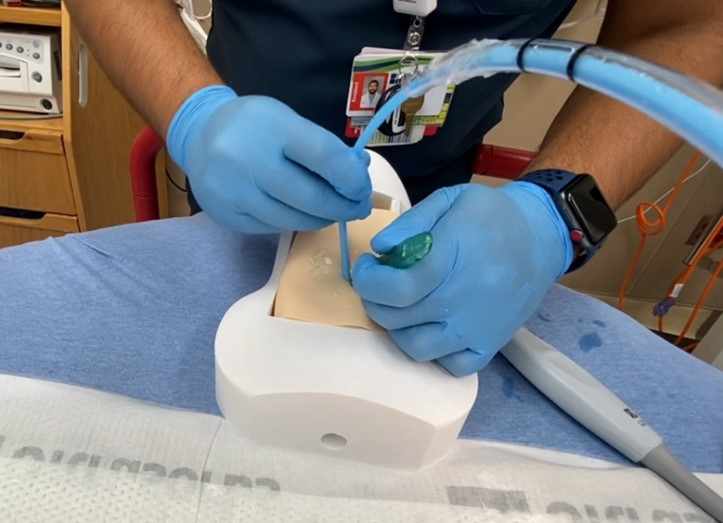

EM physicians are familiar with the technique of performing cricothyrotomy after identifying the CTM by palpation. In 2012, Keith Curtis and colleagues described a novel technique of ultrasound-guided, bougie assisted cricothyrotomy in cadavers.7 In this study, operators viewed the laryngeal cartilaginous structures including the CTM with the linear ultrasound transducer in long axis, the CTM was cut with a scalpel under active ultrasound guidance, then the bougie and endotracheal tube (ETT) were passed. This study reported a success rate of 20/21 attempts and an average time to completion of 26.2 seconds. Others have described ultrasound guidance for percutaneous tracheostomy with the probe in a transverse orientation on the neck.8 Ultrasound has been shown to improve localization of the CTM, increase success rate and decrease complications of cricothyrotomy.2,3,9

A Novel 3-D Printed Model for Ultrasound-guided Cricothyrotomy Training

Procedural training for ultrasound-guided cric has been described on cadavers, animal-derived and combination plastic/meat models, each model with its own advantages and drawbacks for use as a training model.4,5,6 Cadavers are realistic, but expensive, difficult to transport, and not re-usable. Animal derived and meat models also provide realistic anatomy but can be difficult to obtain and to store.

Here we describe a novel model for US-guided cric training that uses 3-D printed structures to provide the realism of cadavers, and the re-usability and durability of synthetic models.

The model can be re-created by downloading the model for 3-D printing, and following the following steps:

- Print the neck model and riser blocks (used to vary the depth of pre-tracheal soft tissue, if desired) on the 3-D printer out of hard plastic polylactic acid (PLA) or similar material.

- Print the larynx on a 3-D printer out of more flexible thermoplastic polyurethane (TPU) or similar material. This allows for a more realistic feel of passing the tube through the larynx, without rigid plastic to for the tube to get caught on.

- Ballistic gel is available commercially with various firmness. Gel that mimics fat tissue works well for this application. Melt the gel in a pot to create slabs of gel of the desired thickness of pre-tracheal soft tissue. This model allows up to approximately 2.5 cm of pre-tracheal soft tissue. Once cool, cut the gel into slabs that fit the model.

- Create an artificial cricothyroid membrane on the model by covering the space for the CTM with a layer of tape.

- For a simulated difficult cricothyrotomy, consider placing the model larynx directly into the neck model without riser blocks behind it. This allows for the largest amount of space in front of the larynx to be filled with ballistic gel acting as pre-tracheal soft tissue.

- Apply generous amounts of ultrasound gel on top of the model larynx, and on top of the ballistic gel to optimize ultrasound images.

- Cut a piece of commercially available artificial skin to size to cover the ballistic gel and complete the model.

In contrast to native cartilage, which is hypoechoic with posterior shadowing, the plastic model of the thyroid cartilage and cricoid cartilage appear hyperechoic with more dense posterior shadowing (below). This model performs well as an ultrasound-guided cric training model. It has realistic anatomy. It models a patient with difficult to palpate anatomy, which are patient who may be difficult to intubate and may be more likely to need cricothyrotomy in the first place. The overlying skin and pre-tracheal ballistic gel can be easily and quickly replaced for the next operator in a training setting. The model allows for performing all the steps of cricothyrotomy including passing the bougie and ETT. The model is durable and re-usable.